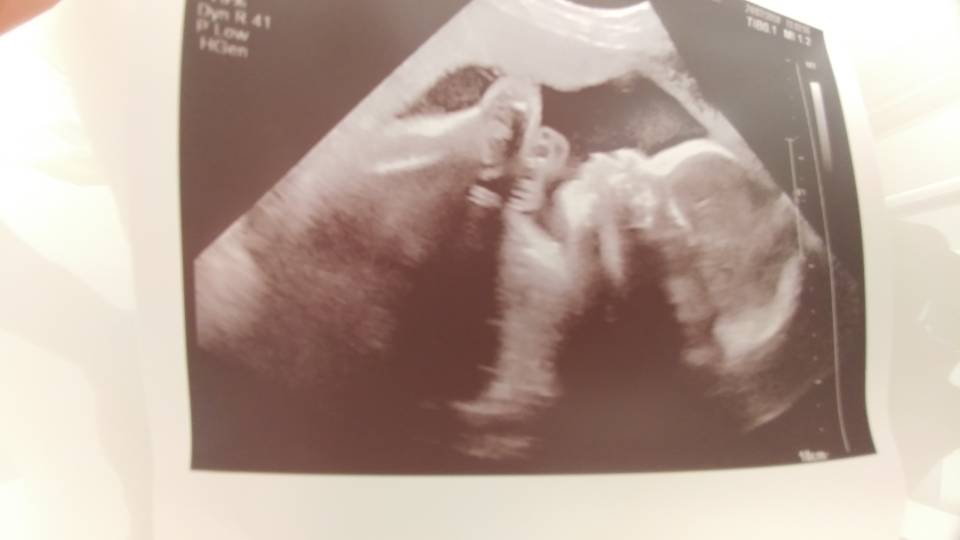

Hej. Byłam dziś na usg (III prenatalne), u mnie na zwykłym aparacie w ramach abonamentu Medicover, ale lekarz z odpowiednimi certyfikatami.

Dziś 28,1 tc ale synek do przodu z pomiarami o 9 i 10 dni. Waga 1420 g. Wszystko ok, chociaż ułożony poprzecznie twarzą do mojego wnętrza więc bardzo trudno było zmierzyć.

Mówił, że przy takim ułożeniu ruchy mogą być bardzo słabo wyczuwalne i faktycznie nie narzekam na kopniaki.

Także duże ufff :)